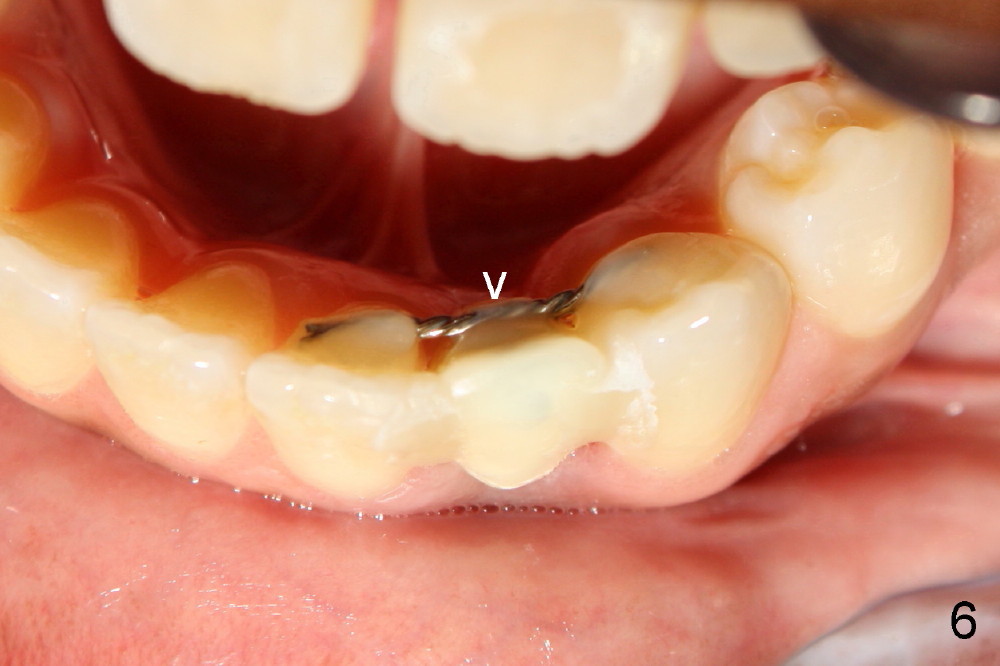

Informed consent is obtained with emphasis of potential damage to the neighboring roots. Two PAs have to be taken with the first pilot drill (1.5 mm) in place for determination of initial trajectory (Fig.2,3). Osteotomy is enlarged coronally with 2 mm pilot drill. Finally a 3x17 mm one piece implant is placed with primary stability, determined tactilely (Fig.4). Immediate provisional is fabricated. To avoid micromovement, the immediate provisional (Fig.5 P) is bonded to the neighboring teeth with composite (*); it is further fixed in place with a lingual retainer (Fig.6 arrowhead).